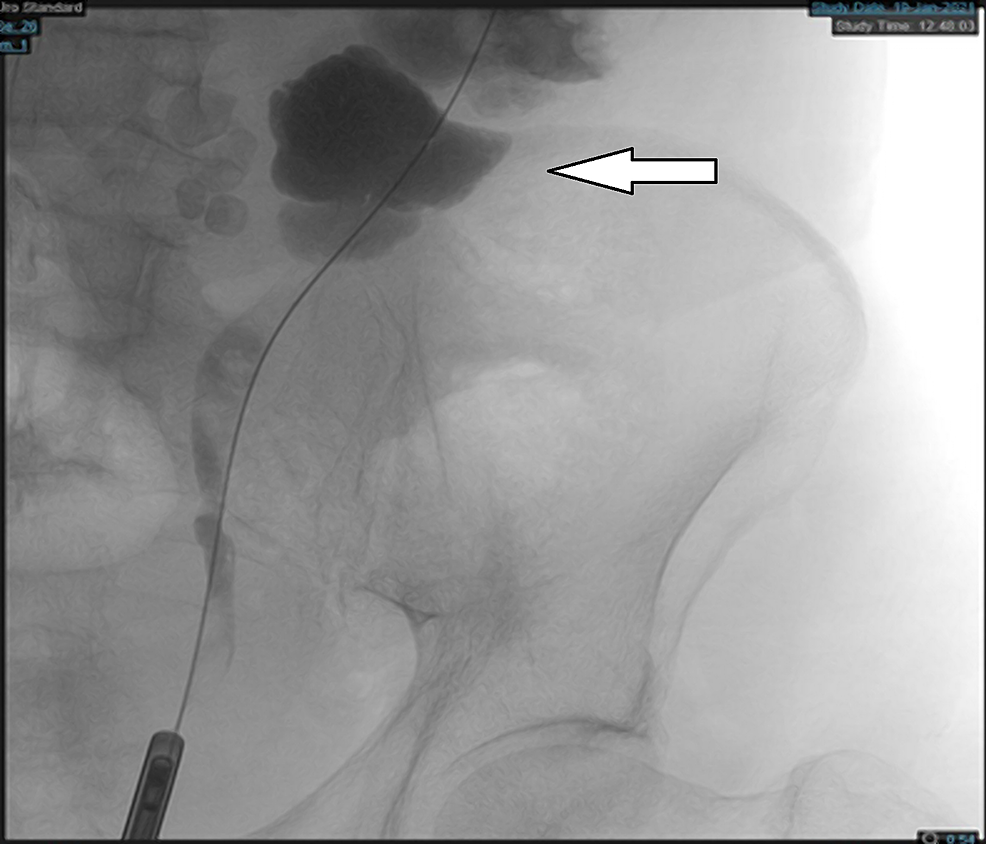

Horseshoe kidney with retrocaval ureter in a 35yearold man with right... Download Scientific Horseshoe Kidney Variants Horseshoe kidney (renal fusion) is when a person is born with the kidneys fused together. Horseshoe kidneys appear as two renal masses located lower in the abdomen than usual, connected by an isthmus of renal tissue. Horseshoe kidneys are the most common fusion defect of the kidneys occurring in approximately 1:500 individuals. A horseshoe kidney is a congenital condition that. Horseshoe Kidney Variants.

Horseshoe kidney with retrocaval ureter in a 35yearold man with right... Download Scientific Horseshoe Kidney Variants A horseshoe kidney is a congenital condition that causes the kidneys to join and form a horseshoe shape. While each child may experience symptoms differently, the most common symptoms of horseshoe kidney include: Horseshoe kidneys are the most common fusion defect of the kidneys occurring in approximately 1:500 individuals. Horseshoe kidney (hsk) is the most common renal fusion, which is. Horseshoe Kidney Variants.